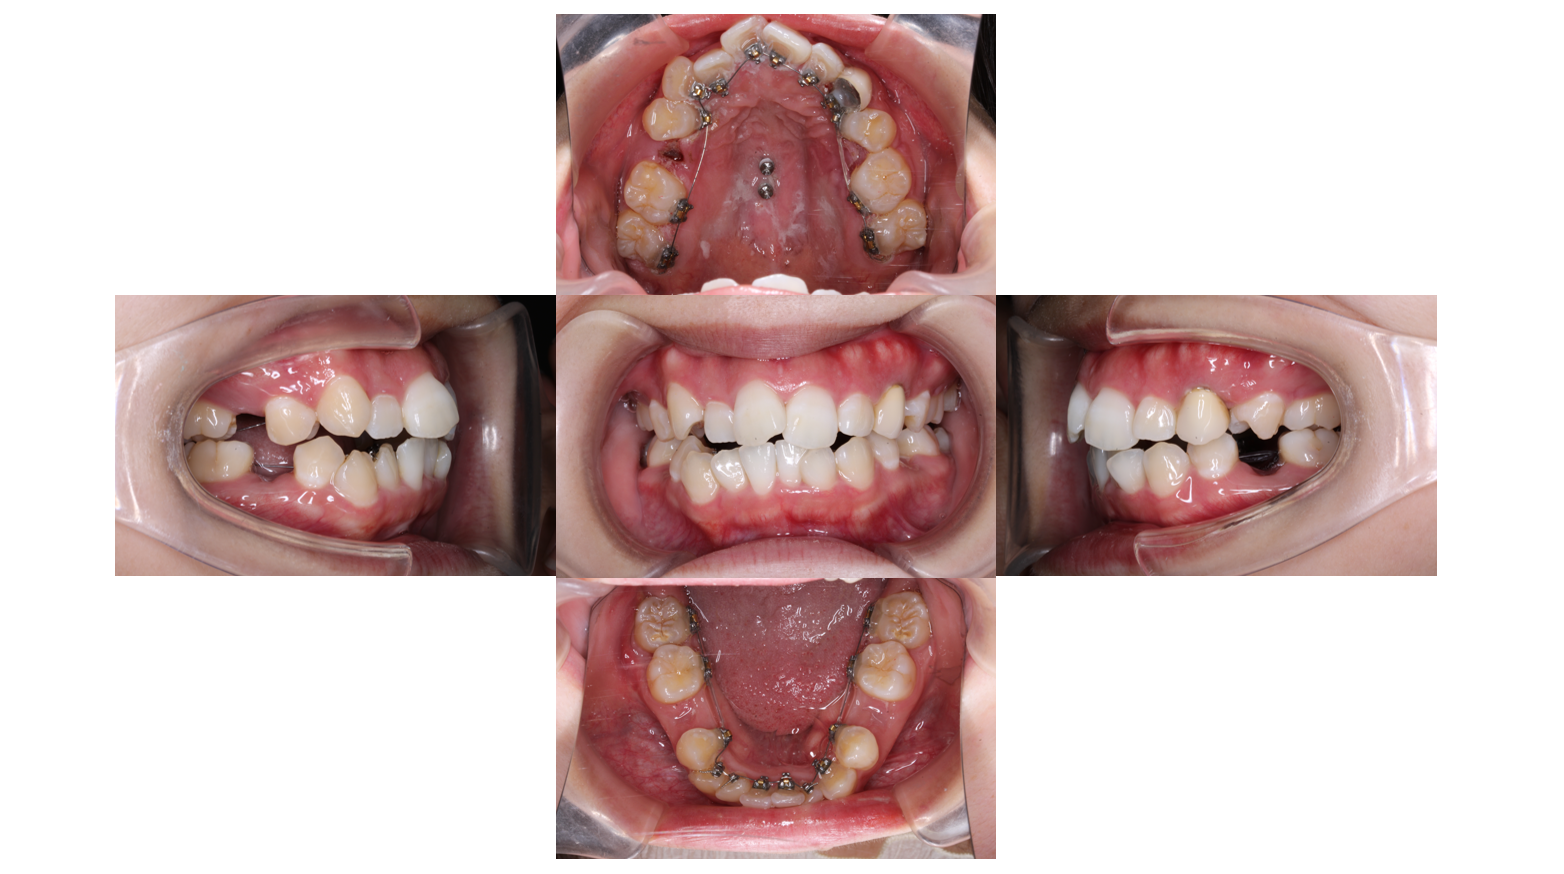

装置装着後

上下裏側に装置がつきました

上あごについているネジは前歯を後ろに下げるために使用します